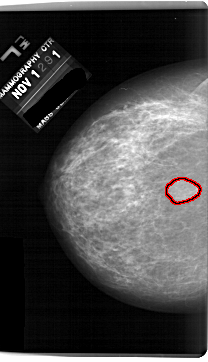

A_1691_1.LEFT_MLO

LEFT_MLO LINES 6466 PIXELS_PER_LINE 4126 BITS_PER_PIXEL 12 RESOLUTION 43.5 OVERLAY

FILE: A_1691_1.LEFT_MLO.OVERLAY

TOTAL_ABNORMALITIES 1

ABNORMALITY 1

LESION_TYPE MASS SHAPE LOBULATED MARGINS CIRCUMSCRIBED

ASSESSMENT 4

SUBTLETY 4

PATHOLOGY BENIGN

TOTAL_OUTLINES 1

BOUNDARY